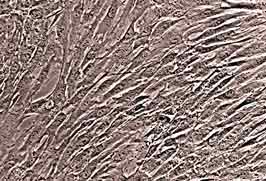

hMSCs are highly useful cells because of their versatility. They are capable of replication as undifferentiated cells and can also differentiate into bone, cartilage, fat, muscle, tendon and marrow stroma. Lonza’s hMSCs are quality tested to differentiate into adipogenic, chondrogenic, and osteogenic lineages when cultured in the recommended differentiation medium. In accordance with the 2006 International Society for Cellular Therapy criteria, Lonza’s hMSCs are now tested to ensure the expression of CD90 and CD73, as well as confirming the absence of HLA-DR and CD19. The cells also express CD29, CD44, CD105 and CD166, and do not express CD14, CD34 or CD45.

hMSCs - human mesenchymal stem cells ©Lonza